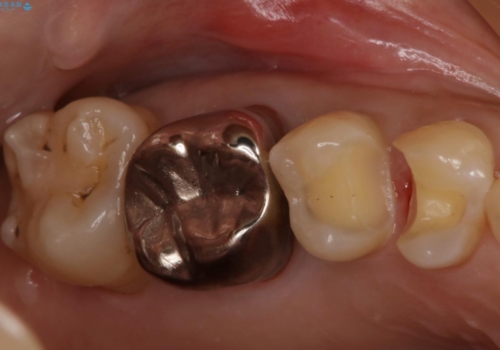

- 右上4、5の歯がしみるのを治したいという主訴で来院されました。精査の結果隣接面う蝕と診断し、適合がよく見ためも良いセラミックインレーでの治療を行いました。

セラミックインレーを入れた後は歯がしみることはなくなり、白く丈夫な被せ物が入り満足いただけました。